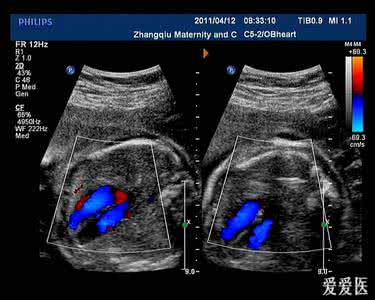

1.2检查方法 孕妇选择仰卧位或侧卧位,使用彩色多普勒超声诊断仪,探头频率设置为3.5~5 MHz,对胎儿心脏进行常规筛查。首先使用二维超成像技术连续扫查法确定胎位、胎心,对胎儿胸腔进行横切扫描获取心脏四腔切面,对心室、心房、房间隔、室间隔、左右房隔瓣联系进行观察。将探头声束略偏向胎儿头侧,观察左右心室流出道切面、心室与大动脉连接关系,连续动态观察主动脉和肺动脉起始部位交叉排列关系、主动脉和肺动脉的相对大小。若发现有心脏异常情况则使用增强型血流成像增强扫描,并邀请专业的心血管超声科医生和产科专业的超声科医生进行会诊,严格遵守心脏阶段分析法要求,再次进行详细的胎儿心脏超声检查,除了重复上述检查步骤外,将探头旋转移动,对主动脉弓、动脉导管弓、三血管、上腔静脉、下腔静脉等切面的检查,必要时可对其他非标准切面进行检查。若胎儿存在胎位不正情况,对检查结果造影响,可择期复查后让孕妇活动30 min,直至切面清晰,可明确判断检查结果。

2.3典型心脏畸形胎儿超声表现 ①完全性房室间隔缺损:超声图像表现为房间隔和室间隔完全性缺失,共同房室瓣悬浮于房室中间;②法洛四联症:室间隔上回声中断,主动脉骑跨于室间隔上,肺动脉瓣狭窄;③大动脉转位:右心室与大动脉相连,左心室与肺动脉相连,四腔心切面正常的“十字交叉”关系消失。

超声检查作为简单、快捷、检出率高、无创的检查方式,被广泛应用在产胎儿心脏畸形的筛查中[2],特别是二维超声与增强血流成像技术的结合可减少彩色血流信号的外溢,提高心脏流速的显示率。